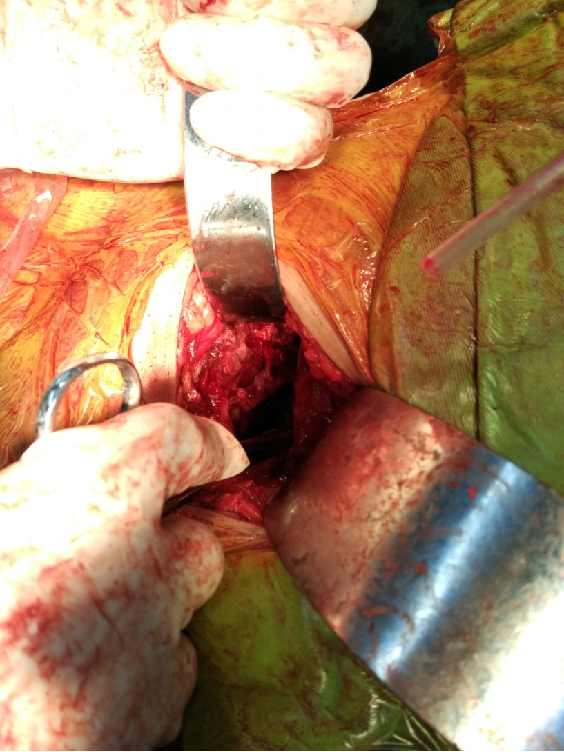

手术入路:取侧卧位或俯卧位,自髂后上棘下方约4厘米处向大转子顶点切一约10 cm唱的弧形切口,切开臀筋膜及阔筋膜,沿臀大肌走行方向钝性分离,在大转子处显露并切断外旋肌和梨状肌,将坐骨神经牵向内侧并小心保护,切断臀小肌及部分臀中肌以显露髋臼后壁及关节囊,清除淤血及纤维性骨痂。